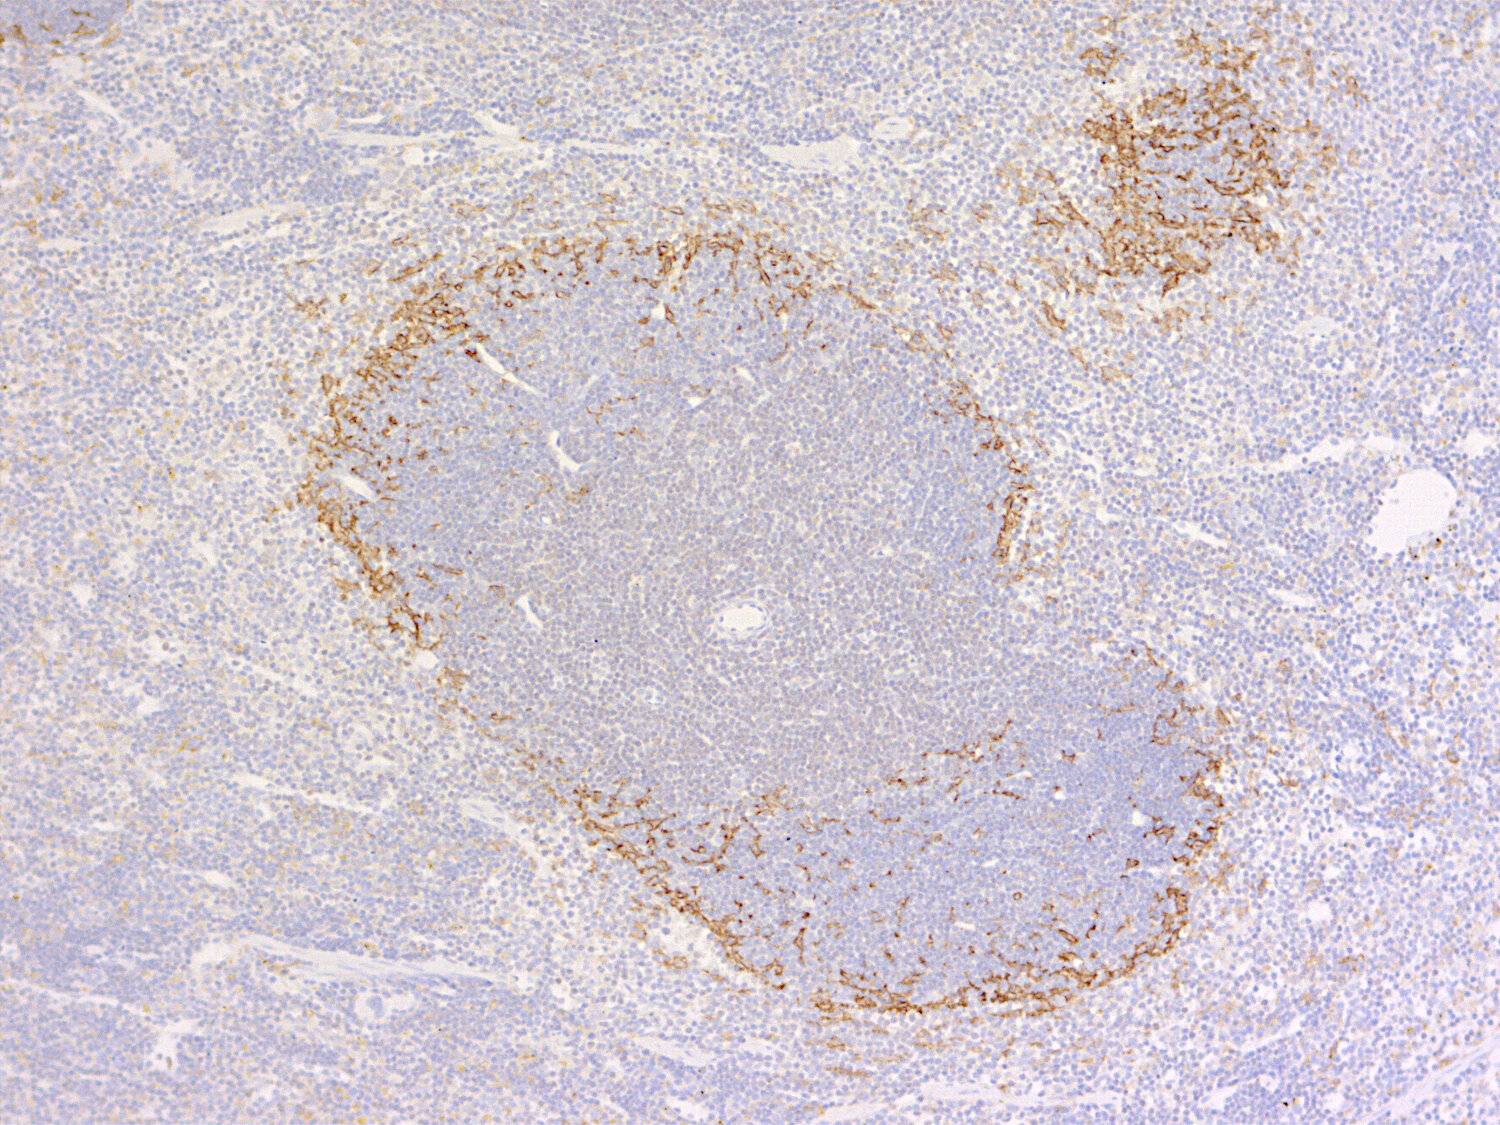

IHC: 1 : 500 (see remarks) gallery

IHC-P: 1 : 100 gallery

CD169 is expressed by marginal metallophilic macrophages (red) but not by F4/80-positive red pulp macrophages (green) in mouse spleen

CD169, also known as Siglec-1 or sialoadhesin, is a cell surface receptor that is most frequently expressed by certain macrophage subsets in lymphoid tissue: the marginal metallophilic macrophages (MMMs) of the spleen and the macrophages in the subcapsular sinus and medulla of lymph nodes (1). To a lesser extent, CD169 is also found on macrophages in liver, lung and colon. CD169⁺ macrophages are involved in immunological tolerance, antigen presentation and defense against infectious agents such as viruses (2) and play a tumor-suppressive role in malignant tumors (3). In the intact brain, CD169 stains subpopulations of macrophages in the choroid plexus, leptomeninges and circumventricular organs (4). CD169 is regulated by contact with plasma proteins, and damage to the blood-brain barrier leads to the expression of CD169 on microglia and macrophages within the parenchyma (4). In glioblastoma, CD169⁺ tumor-associated macrophages were shown to exert an important anti-tumor role by promoting the phagocytosis of apoptotic tumor cells, enhancing the activation of tumor-specific T cells, and supporting lymphocyte infiltration into the tumor microenvironment (5).